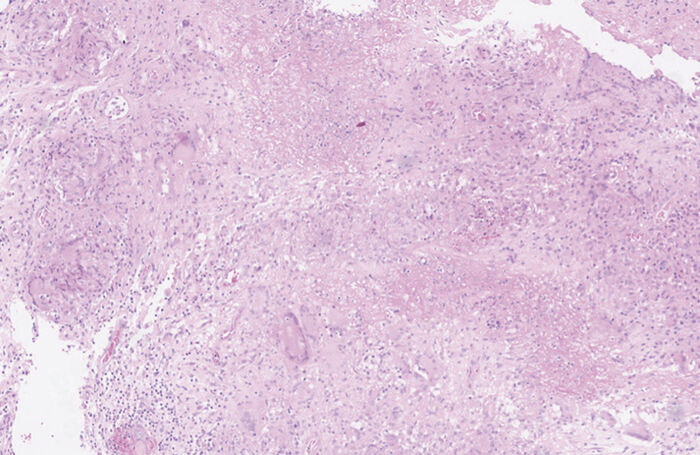

Í svari meinafræðideildar sást vefur úr sári með kröftugri bráðri bólgu og hnúðabólgu (granulomatous inflammation) með drepi (Mynd 1).

Mynd 1a. Smásjármynd af H&E lituðu vefjasýni frá sjúklingi sem tekið er frá sári við endaþarmsop. Hér sést drepmyndandi hnúðabólga.

Mynd 1b. Nærmynd þar sem rauða örin bendir á bólguhnúð (granuloma).